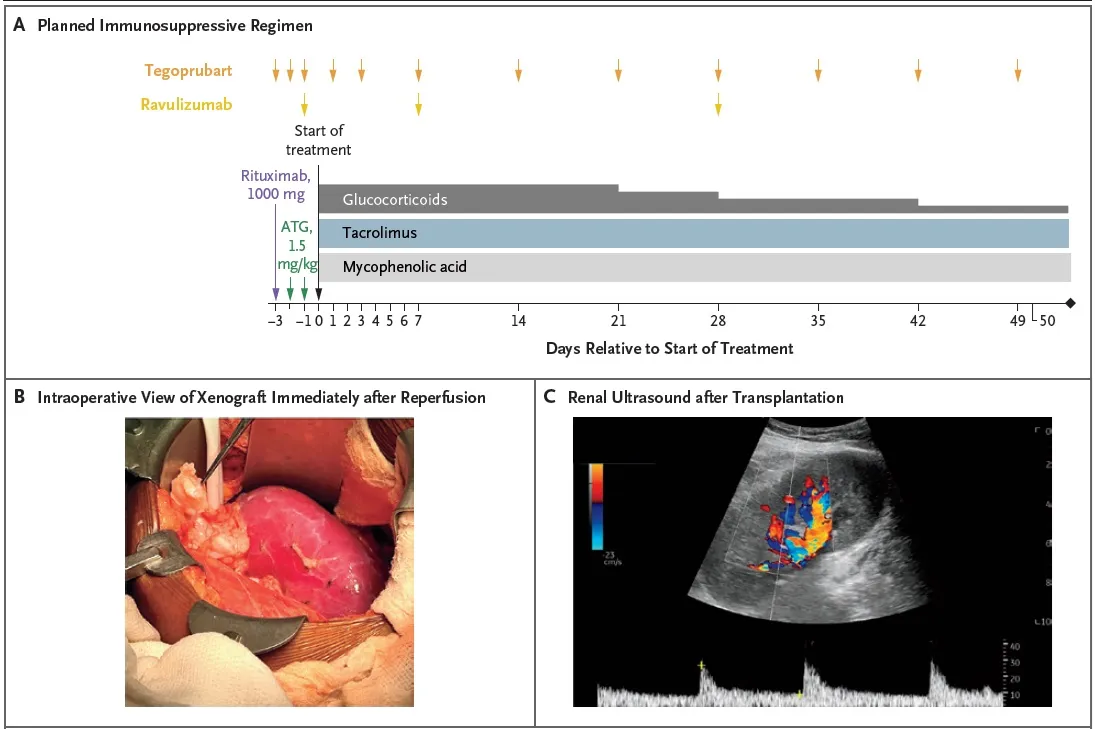

##### Imunossupressão utilizada

Indução

* Timoglobulina (ATG) 1,5 mg/kg

* Rituximabe (1000 mg)

* Tegoprubart (anti-CD154, bloqueia a produção de anticorpos)

* Ravalizumabe (anti-C5)

Manutenção

* Prednisona, tacrolimo e micofenolato

Confere o esquema de imunossupressão utilizado, bem como achados do intraoperatório: